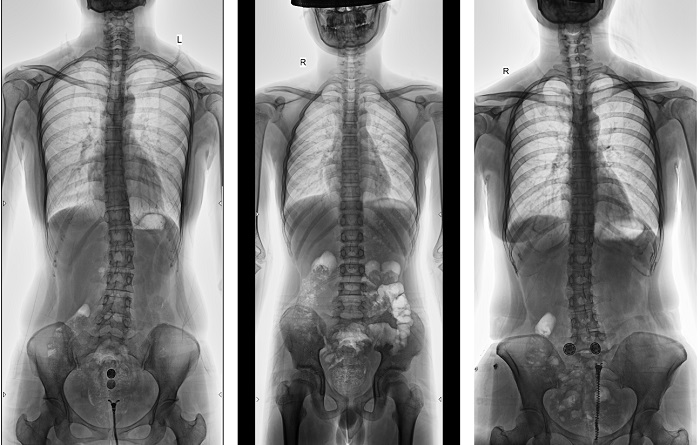

全脊柱成像對于脊柱側(cè)彎的診斷治療、手術(shù)方案的制定具有重要的參考價值;全下肢成像對于髖關(guān)節(jié)、膝關(guān)節(jié)角度的測量、髖和膝關(guān)節(jié)矯形手術(shù)、人工關(guān)節(jié)置換術(shù)等具有重要的參考價值,同時在創(chuàng)傷外科、康復科患者的檢查、診斷和治療中也發(fā)揮著重要作用。

▲全脊柱DR影像